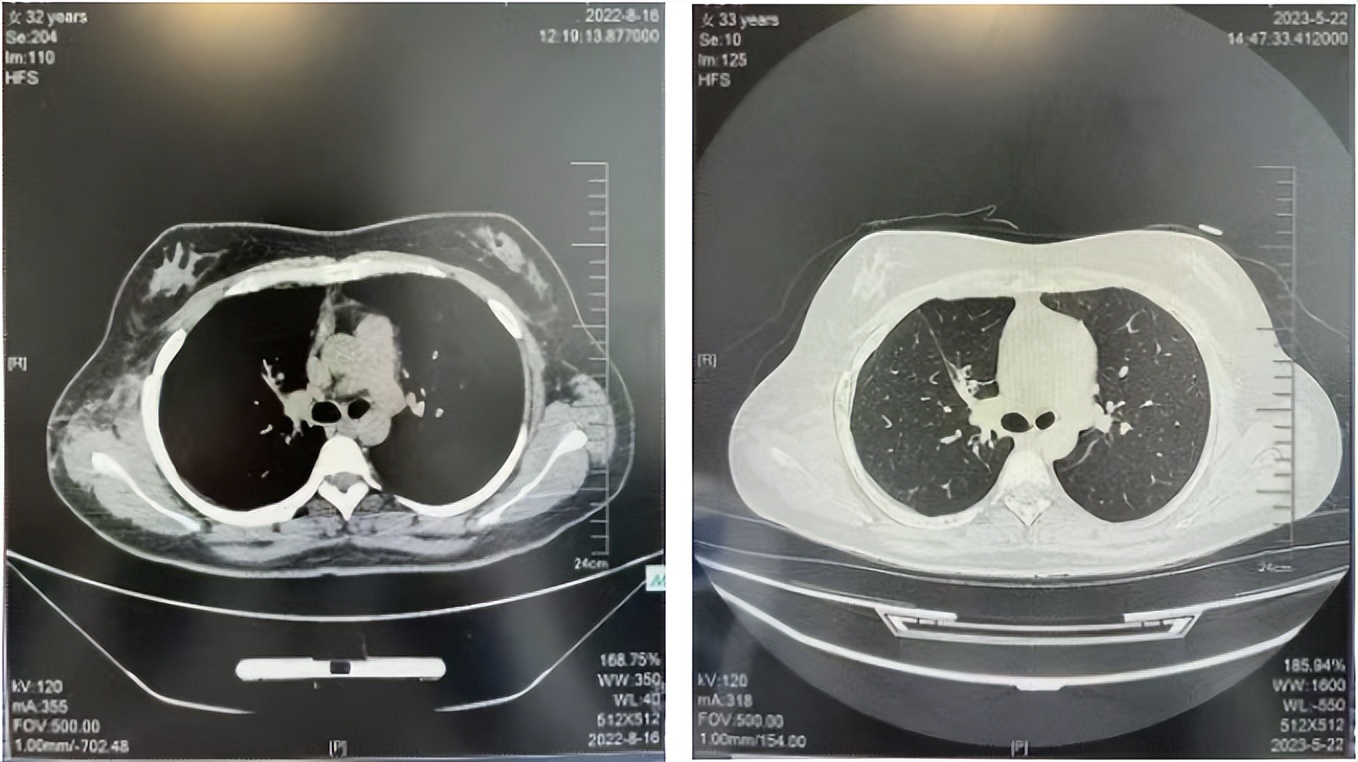

2016年1月复查CT提示支气管截断可见新发小结节,一线治疗采用培美曲塞+DDP方案化疗4周期(培美曲塞3.36,DDP 480mg)。化疗后复查胸部CT:右肺见不规则结节样影,最大层面大小约19mm*8mm,较前比较明显增大,疗效评估PD。2017.3-2017.4予单药多西他赛化疗3周期,疗效评估SD。2018年5月末复查CT提示结节较前增大,评效为PD,2018年6-10月予多西他赛+CBP化疗4周期,疗效评估SD。2022年5月患者出现活动后气短,复查胸部CT示右肺膨胀不良;右侧胸腔积液增多。胸腔积液包埋病理示符合肺腺癌细胞。行NGS基因检测:EML4:exon13-ALK:exon20融合。PD-L1(克隆号22C3)TPS<1%。

2018.07

2022.05

2022.08

2023.05

2024.12